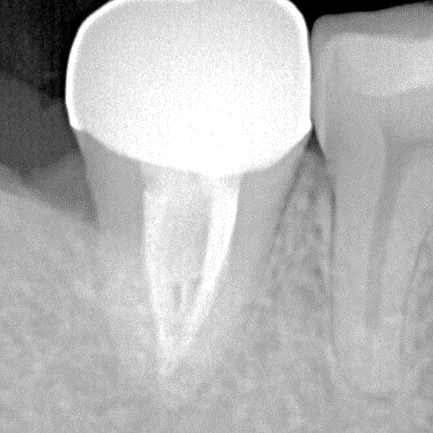

- 診斷與評估:牙醫透過X光片和臨床檢查確認受影響的牙髓狀態。

- 根管填充:用專業材料填充清潔後的根管,封閉以防微生物再次入侵。

- 牙齒重建:通常會使用全瓷冠來保護治療後的牙齒,增強其結構強度。